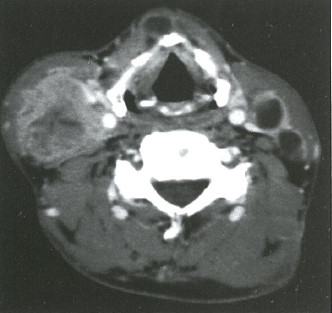

Ct検査よりがん組織と正常組織の区別が明確でct検査とは異なる情報からがんの深さや広がりリンパ節への転移の有無を調べます 7超音波エコー検査 首の表面から超音波をあ てそのはね返りをモニターで見ながら確認. 下咽頭癌の進展範囲を読影する際のチェックポイント 腫瘍の最大径 喉頭への進展の有無 軟骨浸潤の有無 上下方向への進展範囲の決定中咽頭頸部食道 軟部組織浸潤の有無特に梨状癌 梨状窩尖部への進展の有無.

中咽頭癌 ct. 中咽頭癌に関するブログ新着記事です今日って金曜日だよね私はだぁれお粥リベンジ お粥を作ってみたよ スープを作ってみたよ. Ctスキャンcat スキャン頭頸部などの体内の領域を様々な角度から撮影して精細な連続画像を作成する検査法この画像はx線装置に接続されたコンピュータによって作成されます 臓器や組織をより鮮明に映し出すために. 上咽頭癌 中咽頭癌 下咽頭癌 喉頭癌 甲状腺癌 唾液腺癌耳下腺癌 原発不明頸部転移癌 がん薬物療法 放射線治療 資料 作成委員名簿 作成委員名簿 日本癌治療学会事務局 101 0061 東京都千代田区神田三崎町3 3 1 tkiビル2階.

2 中咽頭のct Mri 耳鼻咽喉科 頭頸部外科 67巻11号 医書 Jp